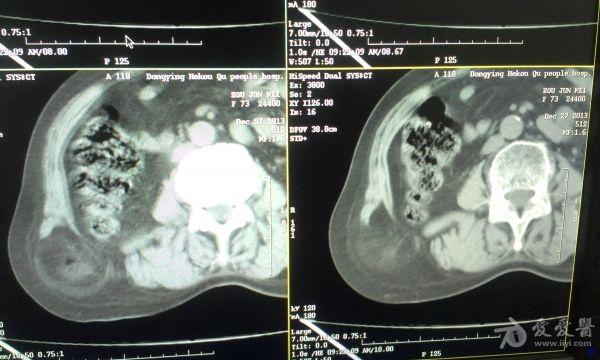

挺经典的腰疝

右腰部包块,随呼吸可运动。

非常经典的ct片,不知是继发于何种原因还是先天性的?里面内容物一般是肠管,很少发生较窄、嵌顿。